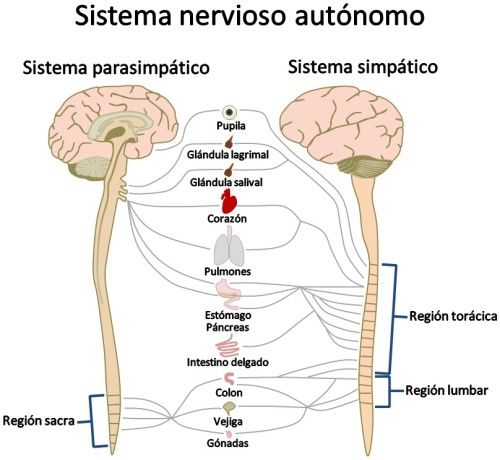

Sistema nervioso autónomo

El sistema nervioso autónomo (SNA) se divide en sistema simpático y sistema parasimpático. El SNA está implicado en la regulación automática de los órganos internos.

El sistema nervioso autónomo, junto con el sistema neuroendocrino, se encarga de regular el equilibrio interno de nuestro organismo, bajando y subiendo los niveles hormonales, la activación de las vísceras, etc.

Para ello, lleva información desde los órganos internos hasta el SNC a través de las vías aferentes, y emite información desde el SNC hasta las glándulas y la musculatura.

Incluye la musculatura cardíaca, la lisa de la piel (que inerva los folículos pilosos), la lisa de los ojos (que regula la contracción y dilatación de la pupila), la lisa de los vasos sanguíneos y la lisa de las paredes de los órganos internos (aparato gastrointestinal, hígado, páncreas, sistema respiratorio, órganos reproductivos, vejiga…).

Las fibras eferentes, se organizan formando dos sistemas diferentes, denominados sistema simpático y parasimpático.

El sistema nervioso simpático principalmente se encarga de prepararnos para actuar cuando percibimos un estímulo saliente, activando una de las respuestas automáticas, que pueden ser de huida, congelación o ataque.

El sistema nervioso parasimpático por su parte mantiene la activación del estado interno de forma óptima. Aumentando o disminuyendo su activación según sea necesario.